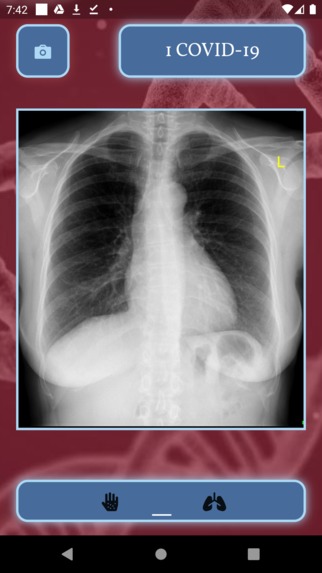

Artificial Insight accurately detects cases of melanoma, a form of skin cancer, through pictures of colored pigments in skin that often resemble moles. Our app also accurately distinguishes between chest x-rays that are either healthy, have pneumonia, or have the coronavirus. The user can choose to either select a photograph of their skin or an image of a chest x-ray. On the left, they can upload a picture of a mole on their skin and the app will tell them whether they have signs of melanoma. On the right, the user can upload an image of a chest x-ray, and the app will tell them whether the x-ray provides indication of pneumonia or COVID-19. The app has an extremely rapid diagnosis response for optimal user experience.

Because of this, we decided to create an application that provides easy methods to determine whether one has skin cancer, pneumonia, and/or COVID-19. It is extremely easy for an average citizen to simply take a picture of a mole on their body and use the app to determine whether or not they have signs of skin cancer. Similarly, x-ray machines are readily available in community physician offices, urgent care clinics, and hospital emergency departments, and they can provide images for diagnosis rapidly. According to the UCLA Department of Radiology, chest imaging plays a very important role in the early diagnosis and the treatment planning for patients with suspected or confirmed COVID-19 or pneumonia chest infections. Thus, we hope that our mobile application will allow citizens to be able to diagnose certain diseases early so that they will be able to obtain the treatment they need more rapidly.